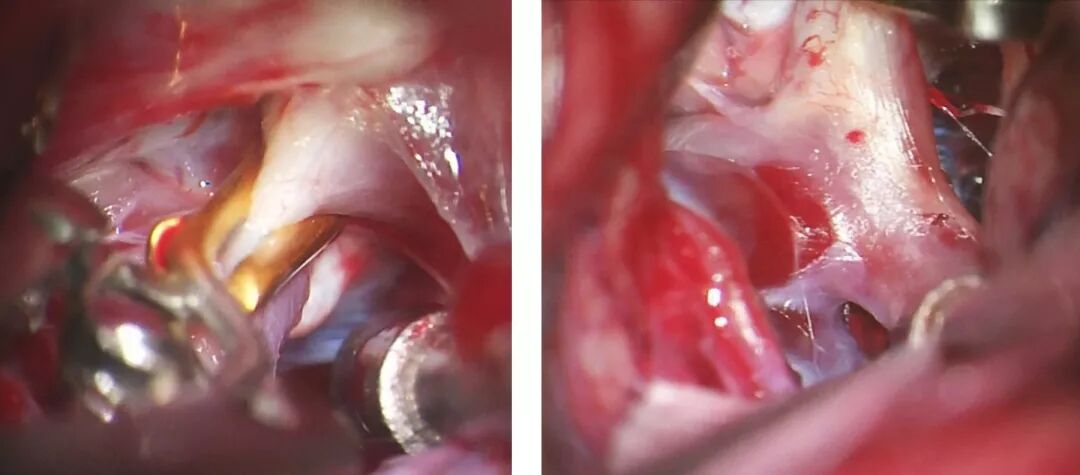

图1:作为夹闭大型后交通动脉动脉瘤(左)时,逆向吸引减压技术的一部分,临时阻断载瘤动脉远端。动脉瘤显著减压后有利于安全和有效地放置永久动脉瘤夹(右)。

图8:在行逆向吸引减压技术夹闭大型后交通动脉动脉瘤时,临时阻断载瘤动脉远端血供。以两枚直角开窗夹将动脉瘤夹闭(内嵌图)。在行逆向吸引减压技术时,于颈部颈内动脉放置球囊导管作临时阻断用。充盈球囊,临时夹在动脉瘤远端阻断颈内动脉,然后通过血管内导管对动脉瘤抽吸减压。